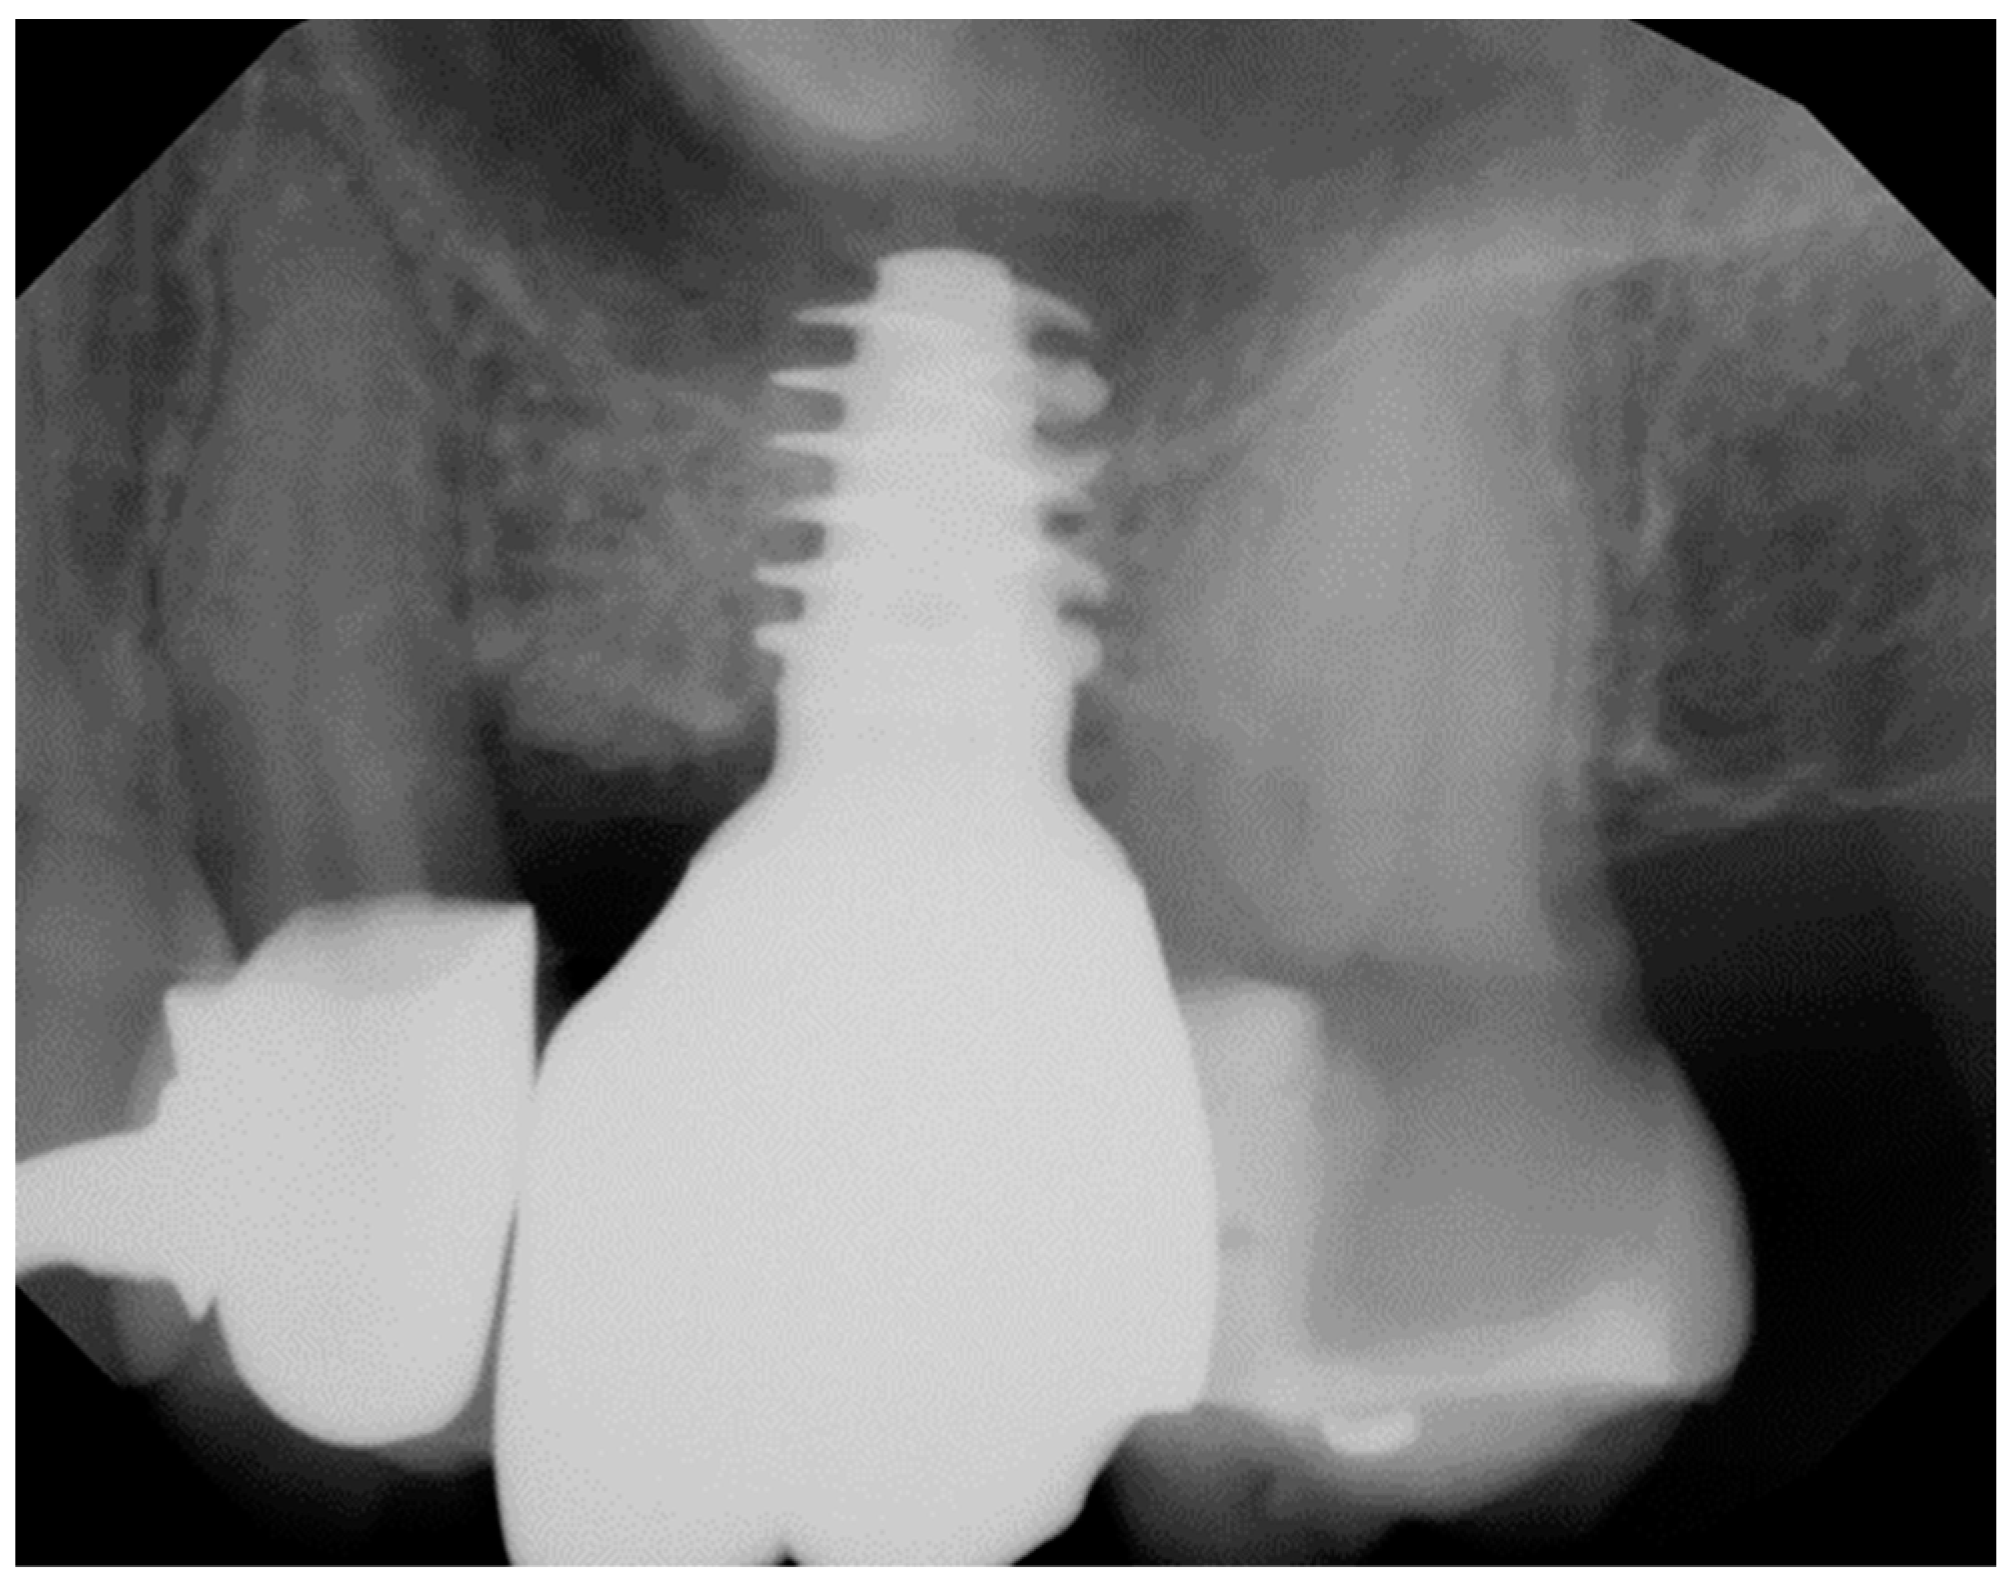

Geometry and diameter also play a significant role in the success of zirconia implants. Excessive implant thread depth is not recommended as the surgical placement might generate high bending forces on the implant body when engaging the bony perimeter of the osteotomy, especially in patients with dense bone (Figure 1).39 Additionally, narrow diameter zirconia implants (<3.75 mm) have been reported to have a higher incidence of fracture compared with the regular diameter implants.40-42

Figure 1. Excessive thread depth design on Straumann TLX titanium implant which is not recommended for zirconia implants.